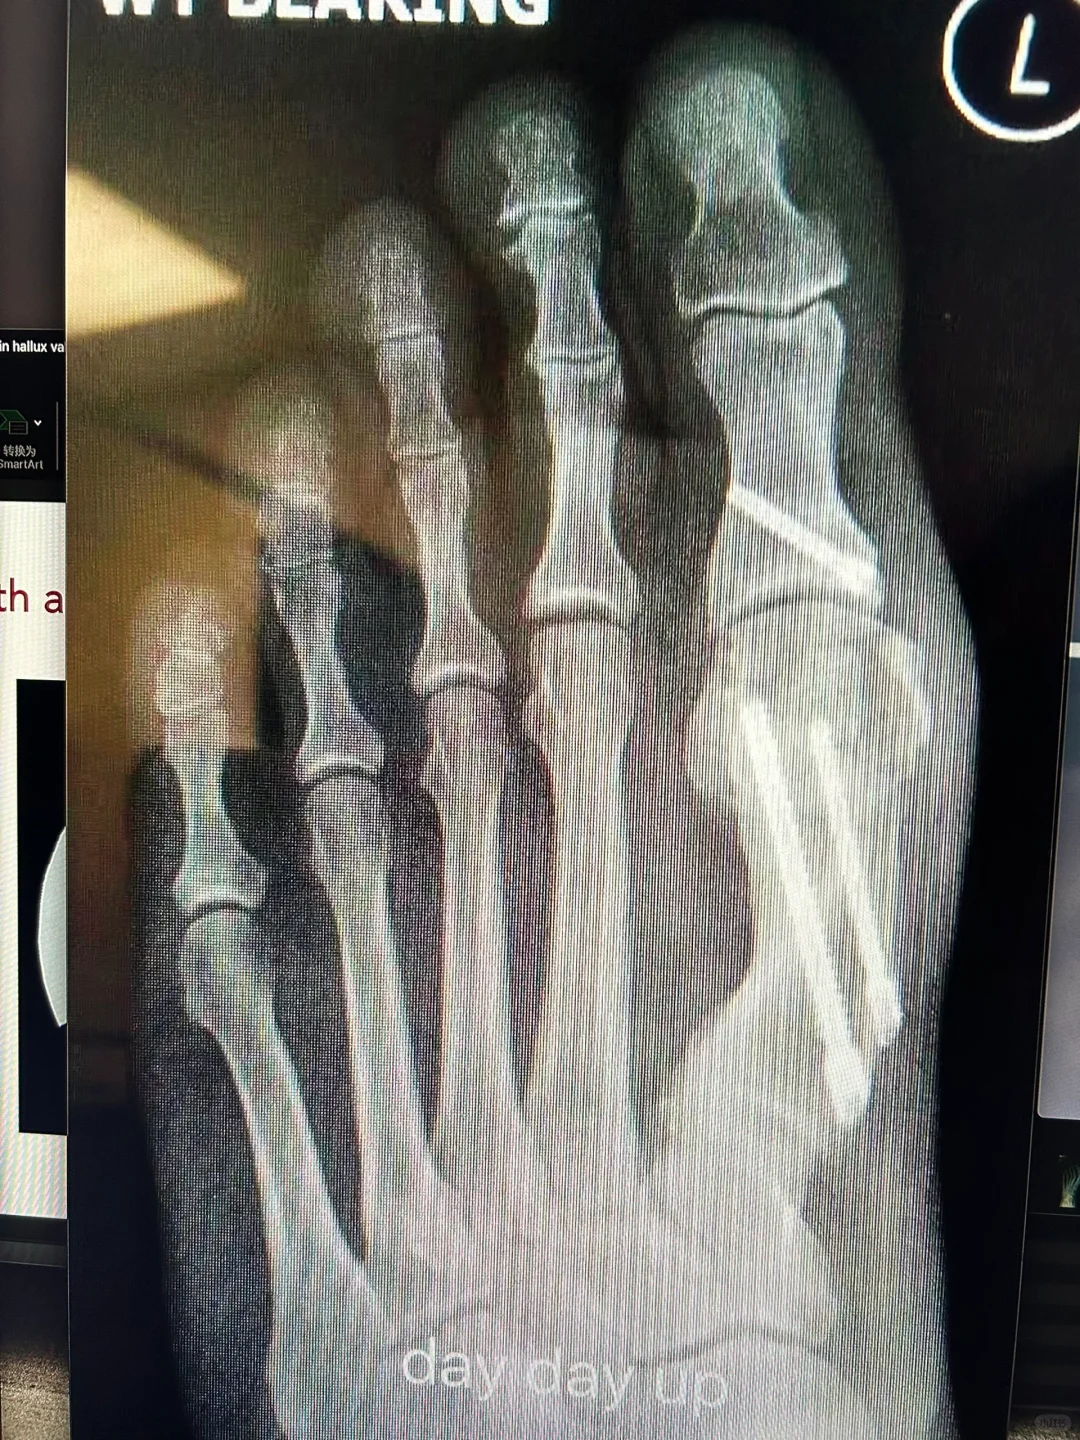

图一是我们的旋转Scarf

图二是我用画图软件模拟的第三代微创,大家可以看到跖骨头的位置是完全一样的,对,是殊途同归,只要把断骨的跖骨头放在那个正确的位置,牢牢固定住,让它在那里愈合,手术效果就是完全一样的。

由于推移量大,下面没有三角区接触,有愈合风险吗?不用担心,看图三和图四,注意那个最长的钉子,穿透了两层坚硬的皮质骨后又进入了跖骨头,in-out-in技术,这个钉子是这个微创技术的灵魂。